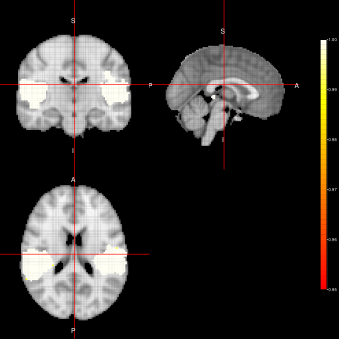

Marginal-FSTS Joint-FSTS

Refer to caption Refer to caption

ACE-FSTS

Refer to caption

Figure 4: Activation Maps obtained for the ”voice localizer” example when using the FSTS algorithm under three different distributions (Marginal, Joint and LTT) related to the state parameter.

From figures 2, 3 and 4, we can see the activation maps obtained for the ”voice localizer” experiment using the method proposed in this work. From those images, we can say that the three algorithms (FEST, FFBS and FSTS) under the three different distributions (Marginal, joint and LTT or average distribution) successfully identify the temporal activation due to voice and non-voice sounds stimulation, nevertheless there are some slight differences among those maps worth mentioning. For instance, the maps obtained when using the FFBS algortihm allows for the identification of a broader activated region from the temporal cortex, however, on the other hand, it allows activations to appear (false-positive activations) on brain regions that should not be involved with this ”voice localizer” experiment. On the other hand, more conservative results seem to be obtained when using FEST and FSTS algorithms, but with less false activations.